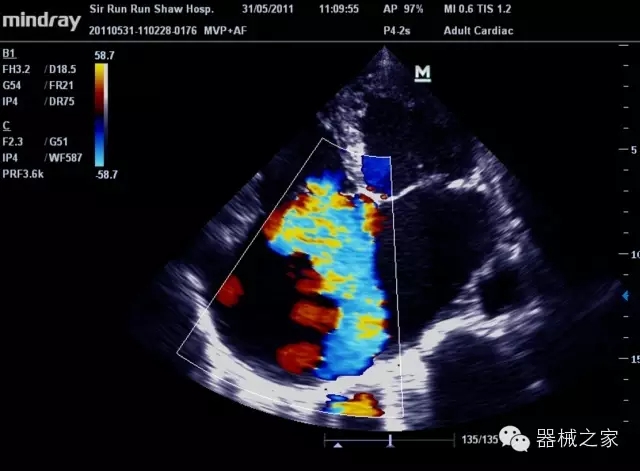

臨床圖片賞析

8倍波束并行處理系統(tǒng)

·在便攜式緊湊平臺(tái)上采用更多倍波束并行接收信號(hào)處理模式,無(wú)論二維還是彩色血流圖像狀態(tài)下,擁有更靈敏的回波頻移捕獲能力,大大提高時(shí)間分辨率,尤其使得心血管表現(xiàn)更為突出;